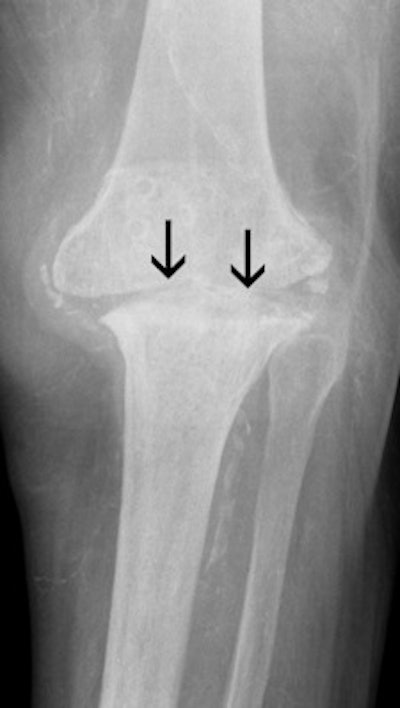

These images show the three most common knee injuries. Left: Osteoarthritis. On the x-ray, the osteoarthritis is clearly recognizable, with the narrowed joint space. Right: Lateral ligament tear. MRI shows the torn lateral ligament (black arrow). The medial ligament (white arrow) is still intact. Copyright of all images: Universitätsklinikum Essen.